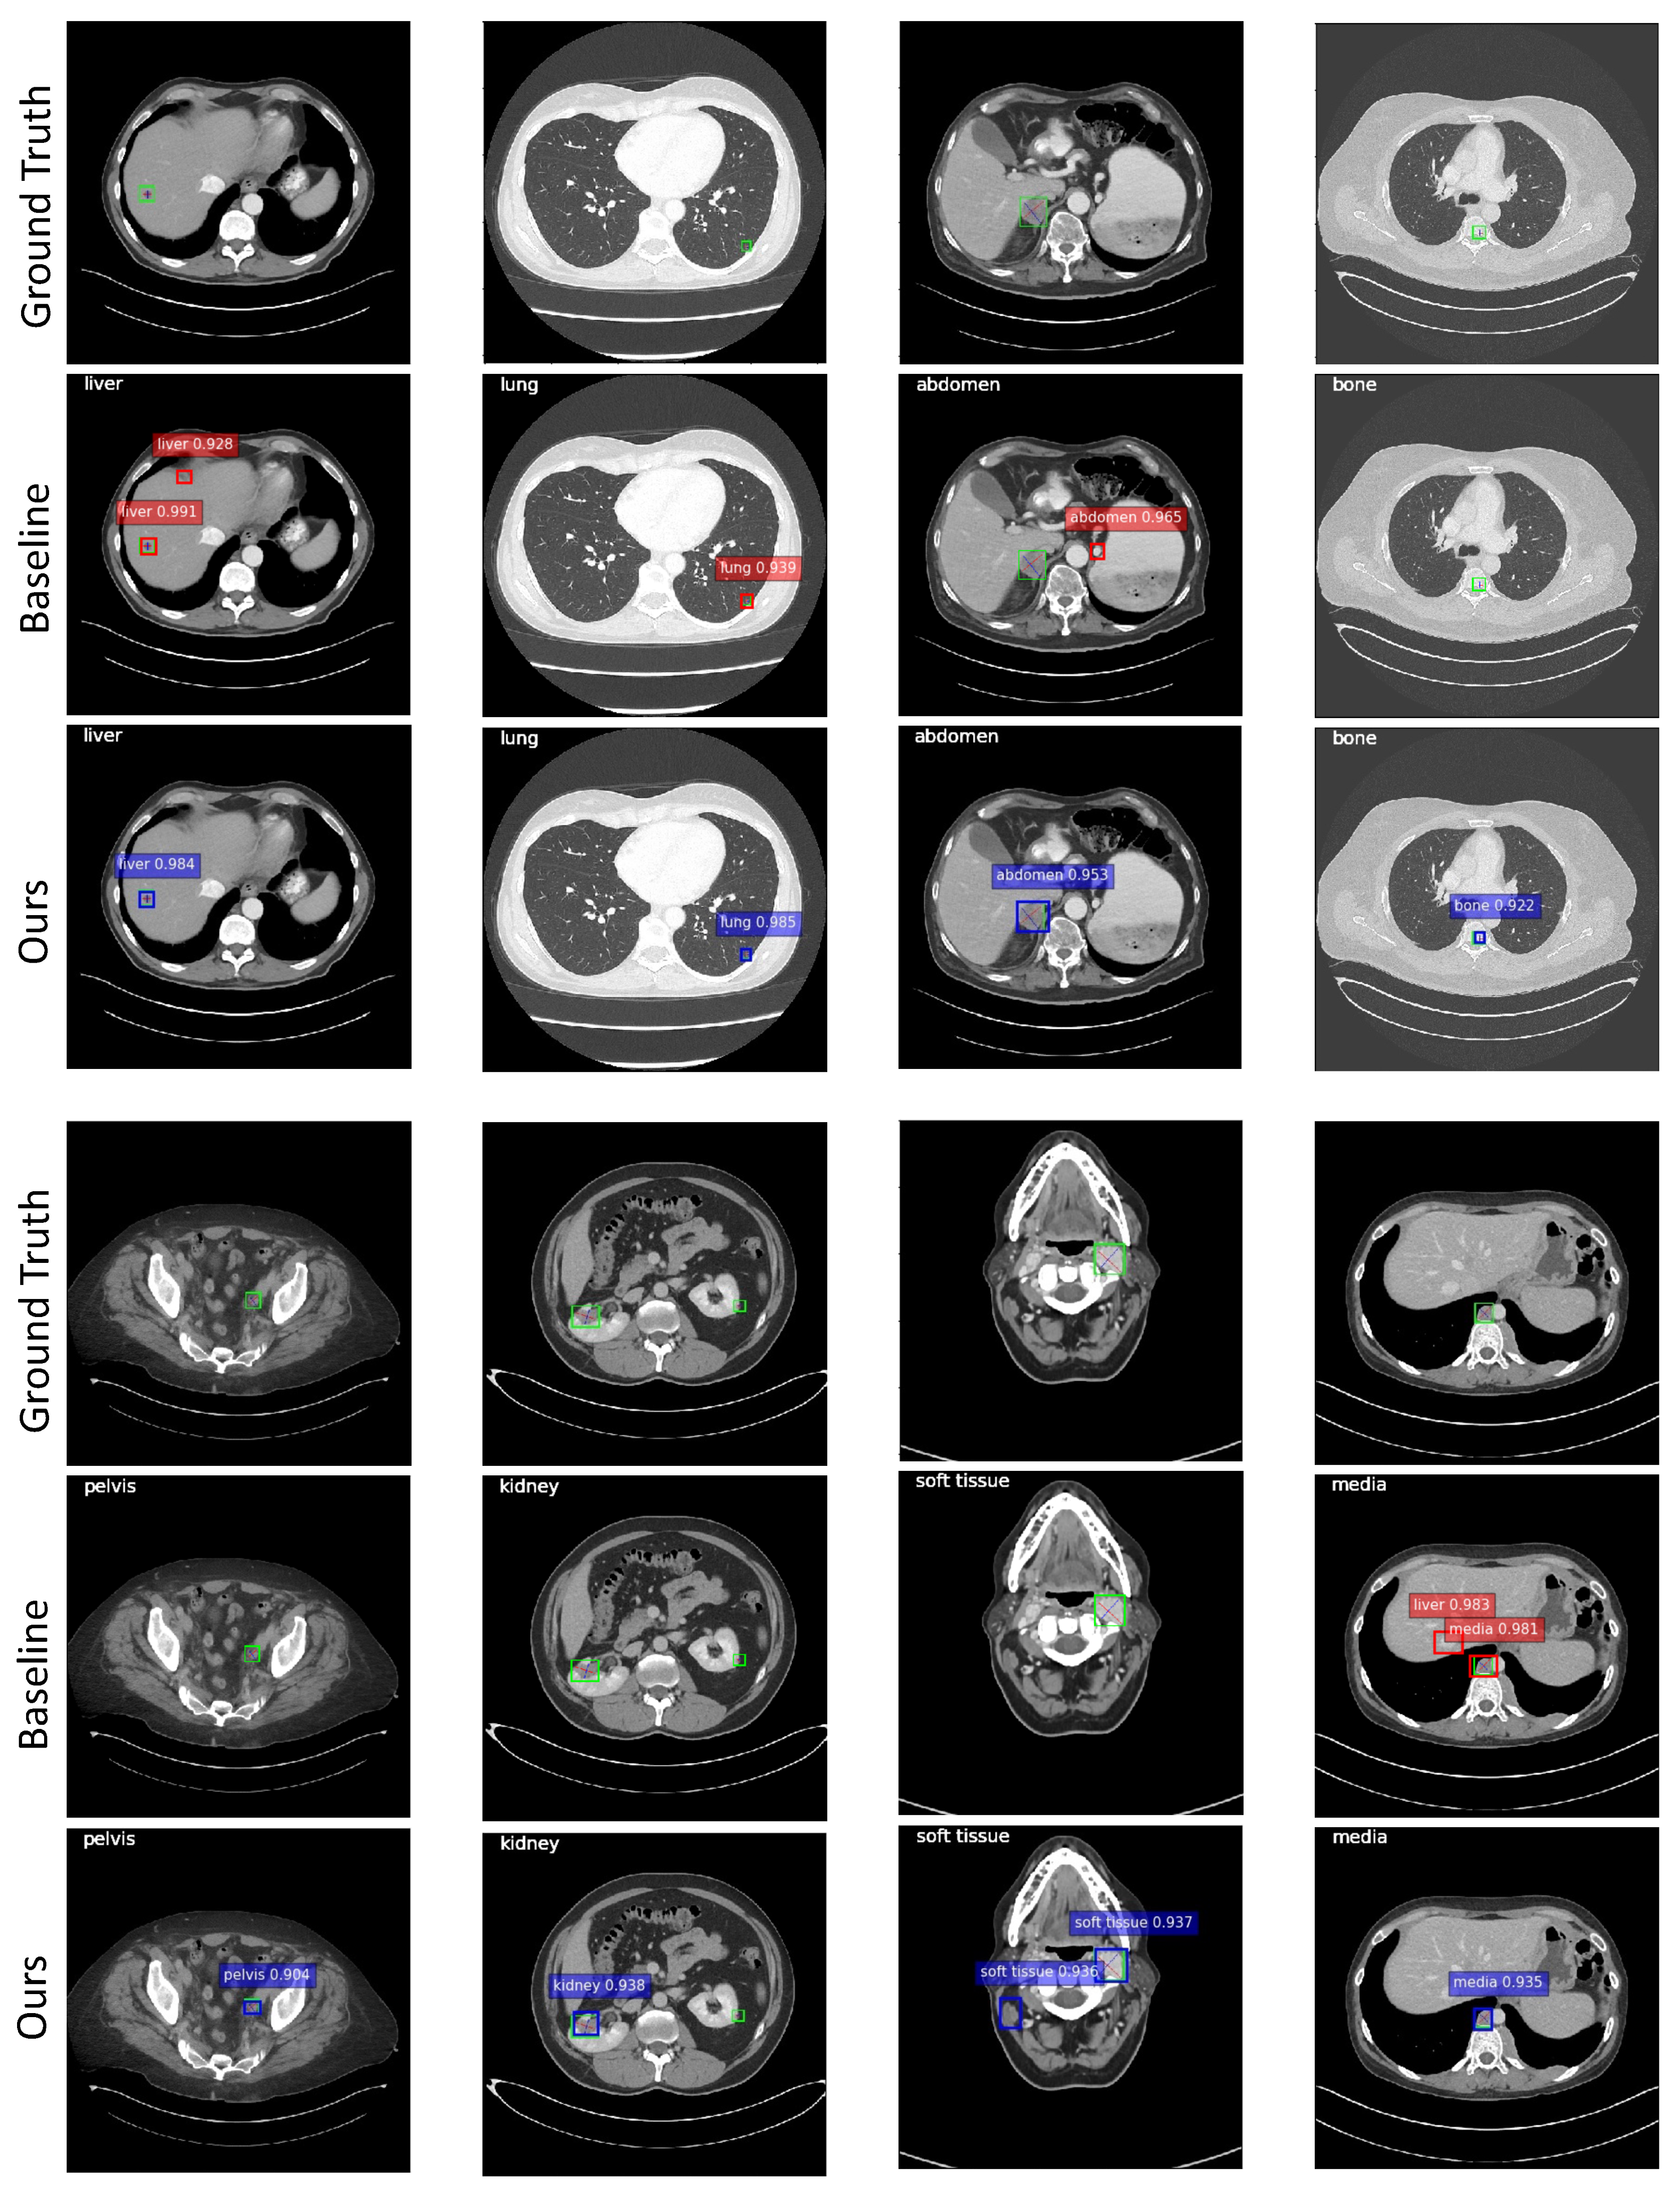

4.2. Multi-Organ Lesion Detection

4.5. Analysis of the Predicted Depth Scores